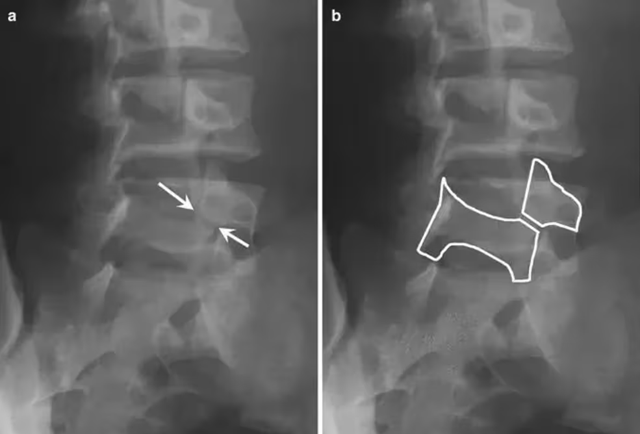

2014年巴西世界杯1/4赛内马尔受伤,据网上传出的内马尔的腰椎X光片,有专家认为,内马尔受伤是,腰椎峡部裂。

简单来说,它是一种腰椎结构异常的疾病,峡部是腰椎的一个重要组成部分负责维持腰椎的稳定,当峡部出现撕裂现象时就形成了腰椎峡部裂,关于腰椎峡部裂的确诊,是需要腰椎双斜位片的,表现为“苏格兰狗脖子”断了。